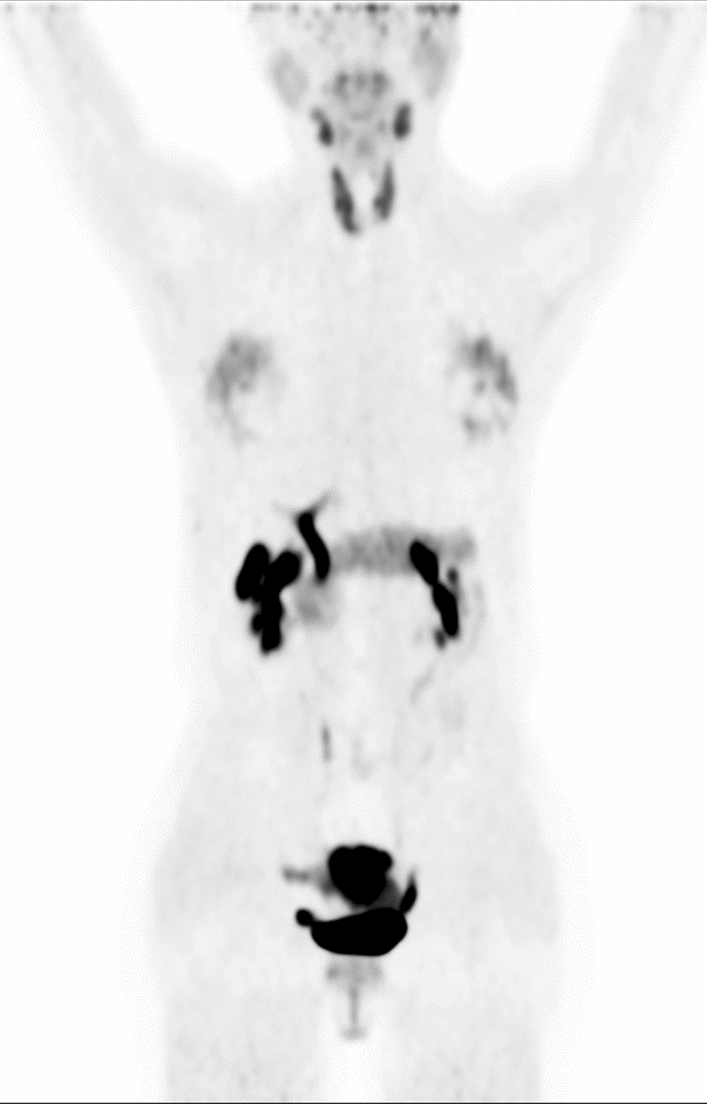

Background: Many patients undergoing [18F] AlF-NOTA-FAPI-04 (18F-FAPI) PET/CT demonstrated diffuse thyroid uptake. These findings created challenges for accurate interpretation due to the limited understanding of physiological and non-oncologic causes of diffuse 18F-FAPI uptake in the thyroid. This retrospective study examined patients who underwent 18F-FAPI PET/CT imaging with diffuse thyroid uptake. It quantitatively assessed normal thyroid uptake, compared 18F-FAPI uptake between normal and diseased thyroids, and explored potential associations with diffuse thyroid uptake. The study may improve the accuracy of 18F-FAPI PET/CT interpretation for thyroid and facilitate appropriate management of diffuse thyroid uptake on 18F-FAPI PET/CT.

Results: A total of 38 patients were included in this study based on the inclusion criteria. The mean SUVmax, SUVmean, and TBR of normal thyroid were 7.09 ± 3.83, 4.24 ± 2.25 and 3.93 ± 1.73, respectively. Quantitative analysis revealed no significant asymmetry in 18F-FAPI uptake between the right and left thyroid lobes (SUVmax: right 6.69 ± 2.96 vs. left 6.54 ± 3.28, p = 0.84; SUVmean: right 4.19 ± 1.73 vs. left 4.18 ± 1.97, p = 0.98), consistent with the diffuse uptake pattern observed. There was no significant correlation between Hashimoto thyroiditis, serum TSH levels, and the degree of diffuse thyroid uptake (all p > 0.05 for SUVmax, SUVmean, and TBR). Furthermore, no association was observed between sex, age, immunotherapy, and diffuse thyroid uptake (p > 0.05).

Conclusions: Diffuse uptake of 18F-FAPI in the thyroid may not significantly relate to Hashimoto thyroiditis or abnormal serum TSH levels. Lesions on 18F-FAPI PET/CT scans might be hard to detect due to the moderate uptake in normal thyroid tissue.